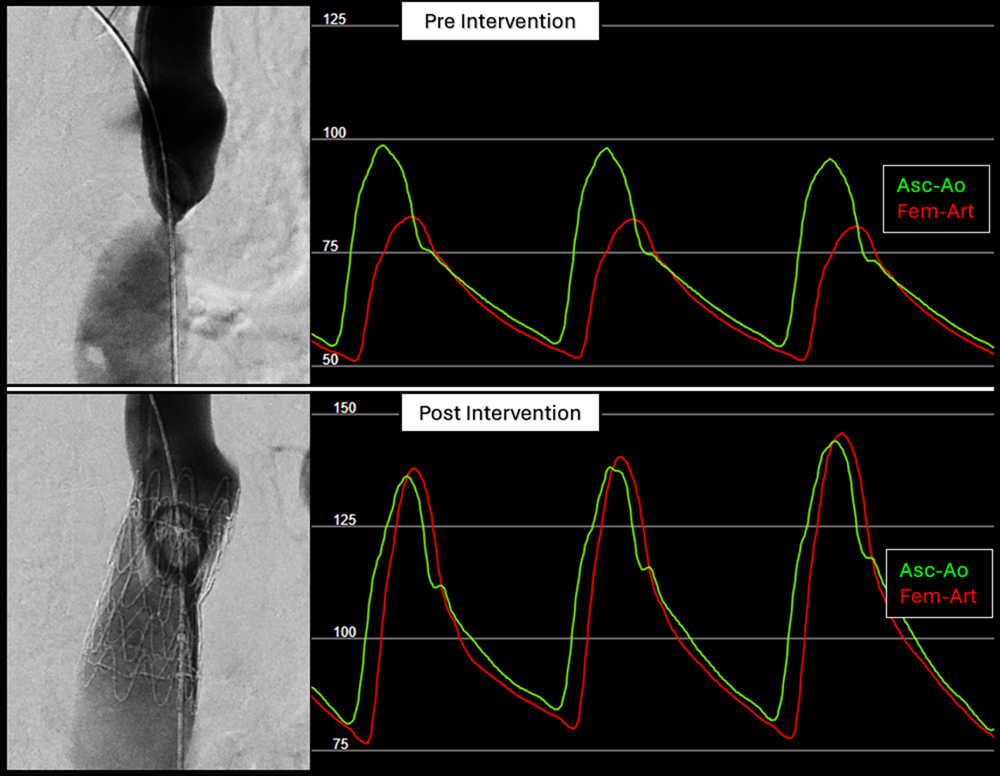

Postintervention invasive measurements revealed no residual Asc-Dsc gradient (median = 0 mm Hg; IQR: 0, 2; P < .001). Several patients demonstrated physiologic pressure reversal (femoral arterial systolic pressure > ascending systolic pressure; Figure 1), consistent with normalization of arch physiology (Figure 1). Negative gradients were not recorded and were documented as 0. The median waist diameter increased from 11 (IQR: 9, 12) to 20 mm (IQR: 18, 22) (P < .001). Aortic isthmus ratio increased from 0.46 (IQR: 0.39, 0.54) to 0.87 (IQR: 0.77, 0.92) (P < .001). No intraprocedural complications occurred.